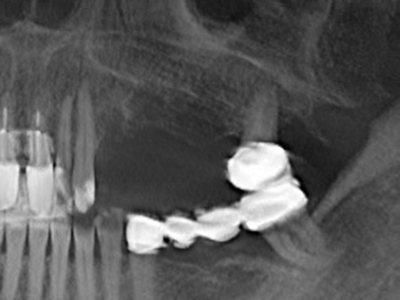

Piezo surgery has additional advantages when harvesting bone blocks. In addition to the high precision with osteotomy described above, the use of the thin saw tips specifically minimizes loss of material. Greater loss of material during harvesting can be expected with the thicker instrument tips, particularly when using Lindemann drills (Lakshmiganthan, Gokulanathan et al. 2012). The basal separation, which is necessary particularly for retromolar block transplants, is simplified by specially designed rectangular saws, with the result that piezo surgery is viewed as a precise, simple and safe procedure for harvesting retromolar bone blocks (Happe 2007) (Fig. 1-12).